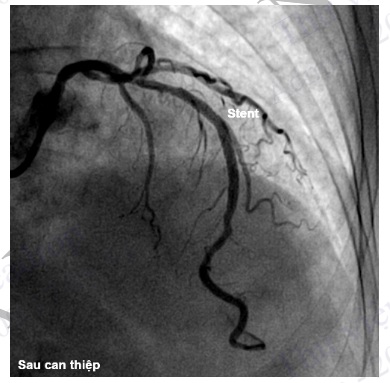

Hình 4.96. Chụp ĐMV trái sau can thiệp đặt stent ĐM liên thất trước cho thấy lòng mạch bị hẹp đã được tái thông